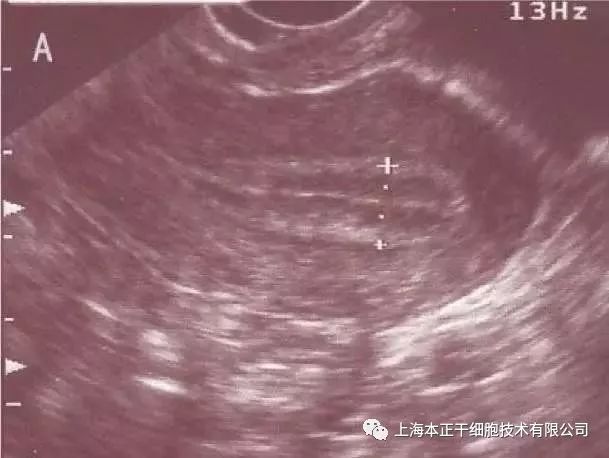

图3:排卵前摘除宫内节育器后子宫内膜变薄

图4:子宫内膜发育良好,低阻力血管达4区。